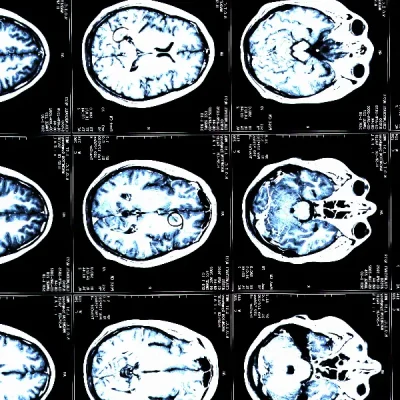

Investigadores vinculados al CIBER han desarrollado una herramienta que permite predecir el riesgo de sufrir un ictus isquémico analizando el perfil de grasas en sangre. El ictus isquémico se produce cuando una arteria que lleva sangre al cerebro se obstruye, y es una de las principales causas de discapacidad y mortalidad.